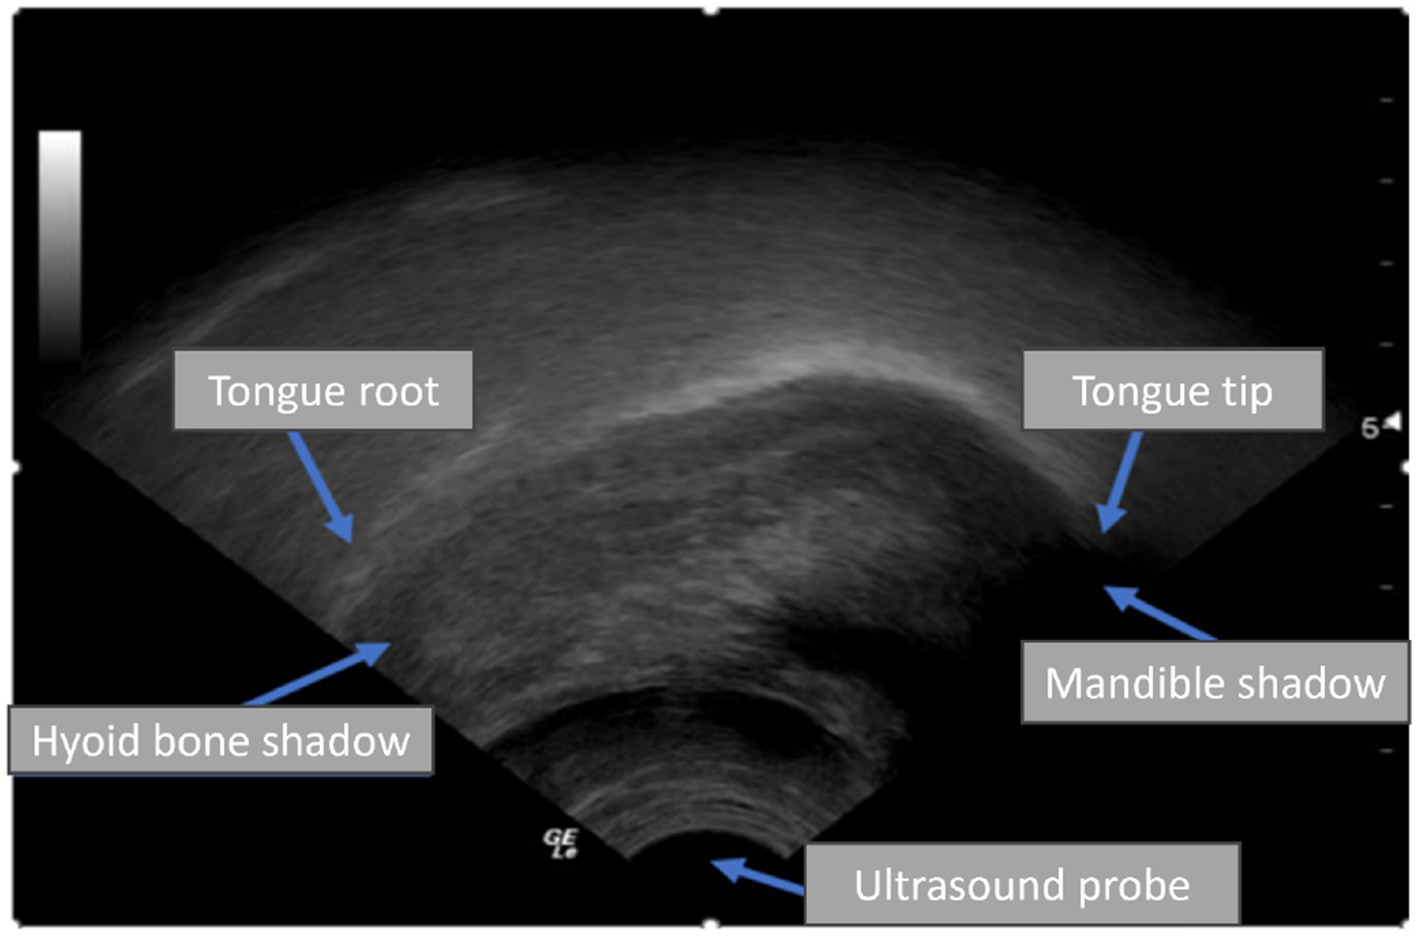

Ultrasound tongue imaging (UTI) has emerged as a viable technique to improve the diagnosis and treatment of SSD. UTI employs a probe positioned beneath the chin to capture real-time midsagittal images of the tongue during speech, facilitating the imaging of tongue shape and motion without radiation or invasiveness (Cleland, 2021; Smith et al., 2023; Hu et al., 2023). UTI is safe, suitable for children, and comparatively portable, making it appealing for paediatric speech therapy. Figure 1 illustrates a typical UTI, where the tongue surface appears as a bright arc against a darker background, with shadows produced by the hyoid bone and jaw. Clinicians and researchers have utilised UTI to deliver biofeedback in therapy and to investigate articulation, especially in those with speech disorders like childhood apraxia or cleft palate, by examining tongue patterns that are not externally observable (Preston et al., 2017). Interpreting ultrasound images traditionally requires manual tracing of tongue contours or professional analysis, both of which are time-intensive and impractical for implementation in every therapy session.

Figure 1

Ultrasound image showing labeled parts of the tongue and related structures: tongue root, tongue tip, hyoid bone shadow, mandible shadow, and ultrasound probe. Arrows point to each labeled area.

Figure 1. An ultrasound scan shows the tongue root and tip in the sagittal plane.